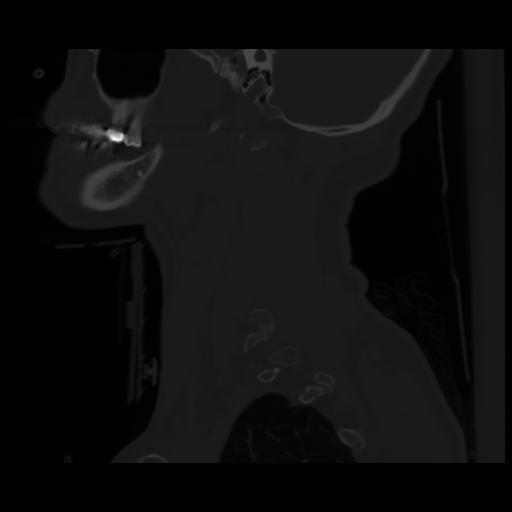

14 P.BLANDAS,,Sagittal,2.000,P.BLANDAS,Sagittal,